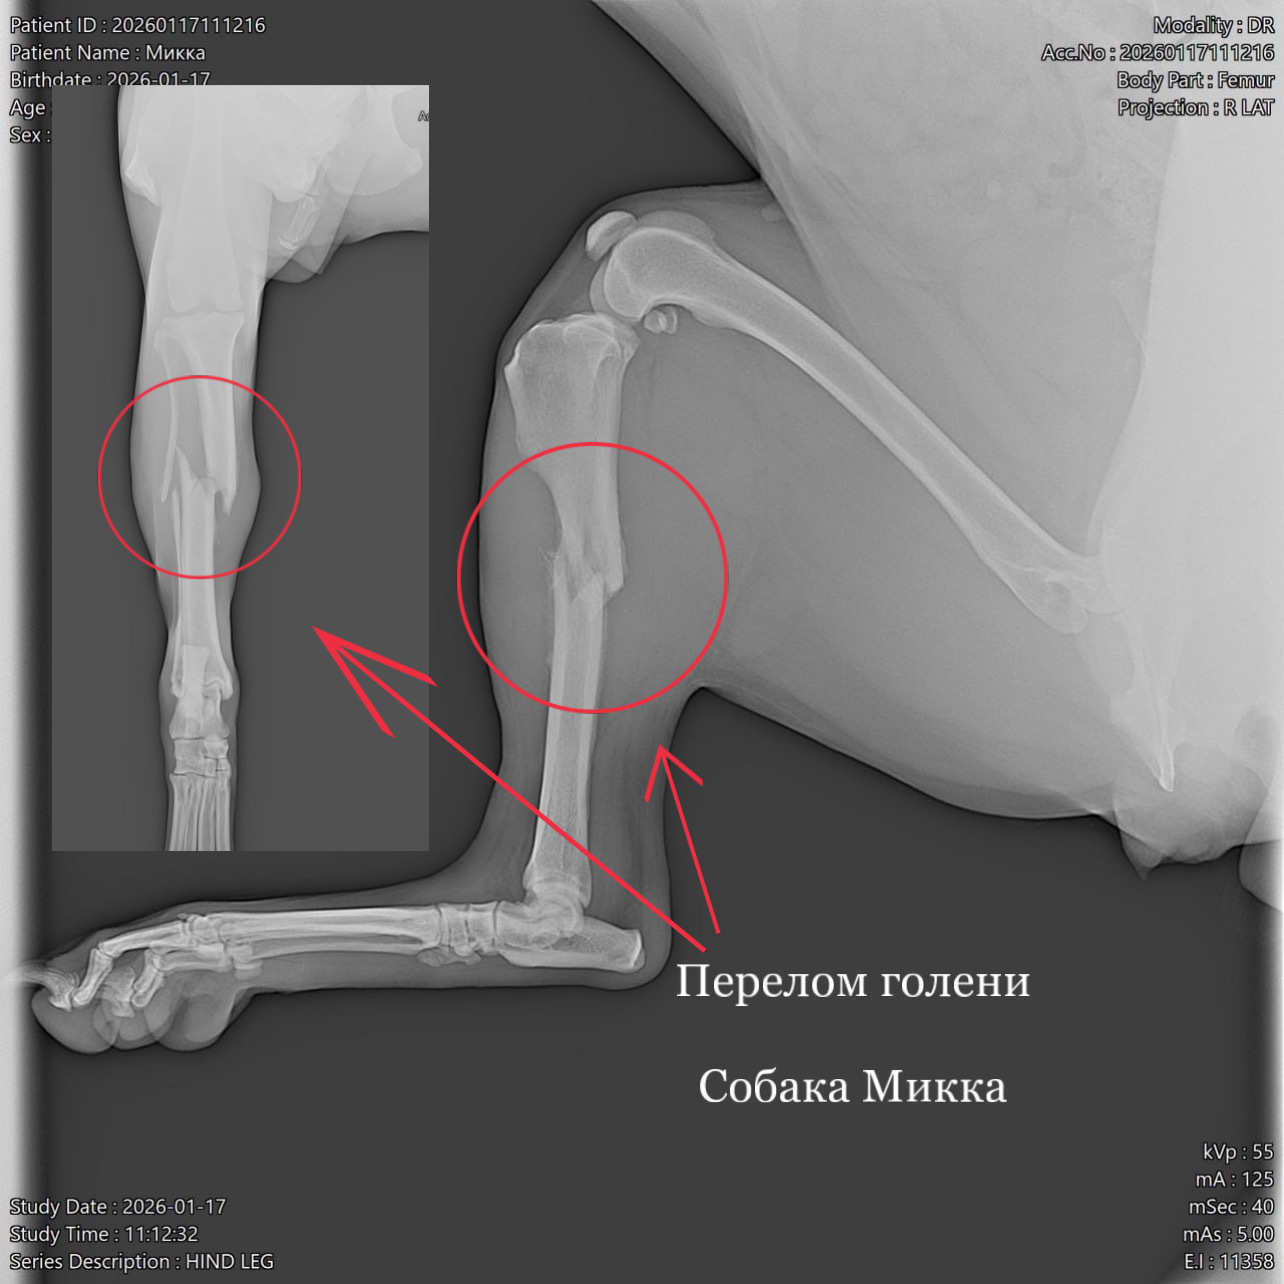

Кане-корсо. Поперечный перелом голени со смещением

В клинику обратилась собака породы кане-корсо (2 года). Со слов владельцев животное убежало из дома на 11 дней, вернулась с висячей конечностью, в течении 3 дней владельцы искали клинику для проведения операции. По результатам рентгенологического исследования выявлен диафизарный поперечный перелом голени со смещением. По согласованию с владельцами провели металлоостеосинтез трубчатых костей накостной пластиной. В ходе операции было обнаружено образование псевдоартроза (ложного сустава), костные отломки были зачищены и репонированы (сопоставлены) согласно их анатомии. Владельцем были даны послеоперационные рекомендации по уходу за животным.